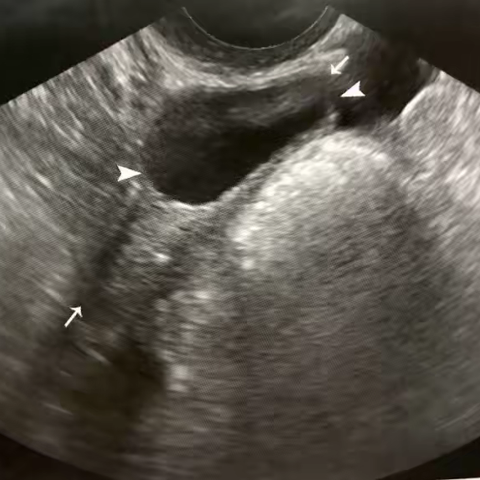

卵巢扭转的超声表现